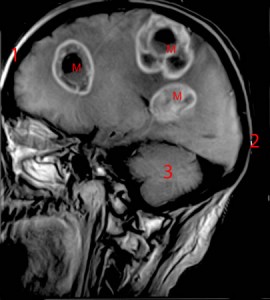

Métastases cérébrales

Quand on évoque la localisation d’un cancer, on parle en fait de l’organe dans lequel le cancer primitif a pris naissance. Tous les cancers sont susceptibles de développer des métastases (tumeurs-filles) dans d’autres organes, notamment les poumons, le foie, le squelette, la peau ou le cerveau.

Dans ces cas-là, la formulation correcte est, par exemple, « cancer su sein avec métastases osseuses », ou « cancer du côlon avec métastases hépatiques », et non pas « cancer des os » ou « cancer du foie ».

Quand plusieurs organes sont concernés par les métastases, le cancer devient « généralisé ».